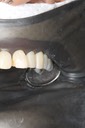

Kyle Chock #15 pre-op

Kyle Chock #15 caries removal

Kyle Chock #15 prep